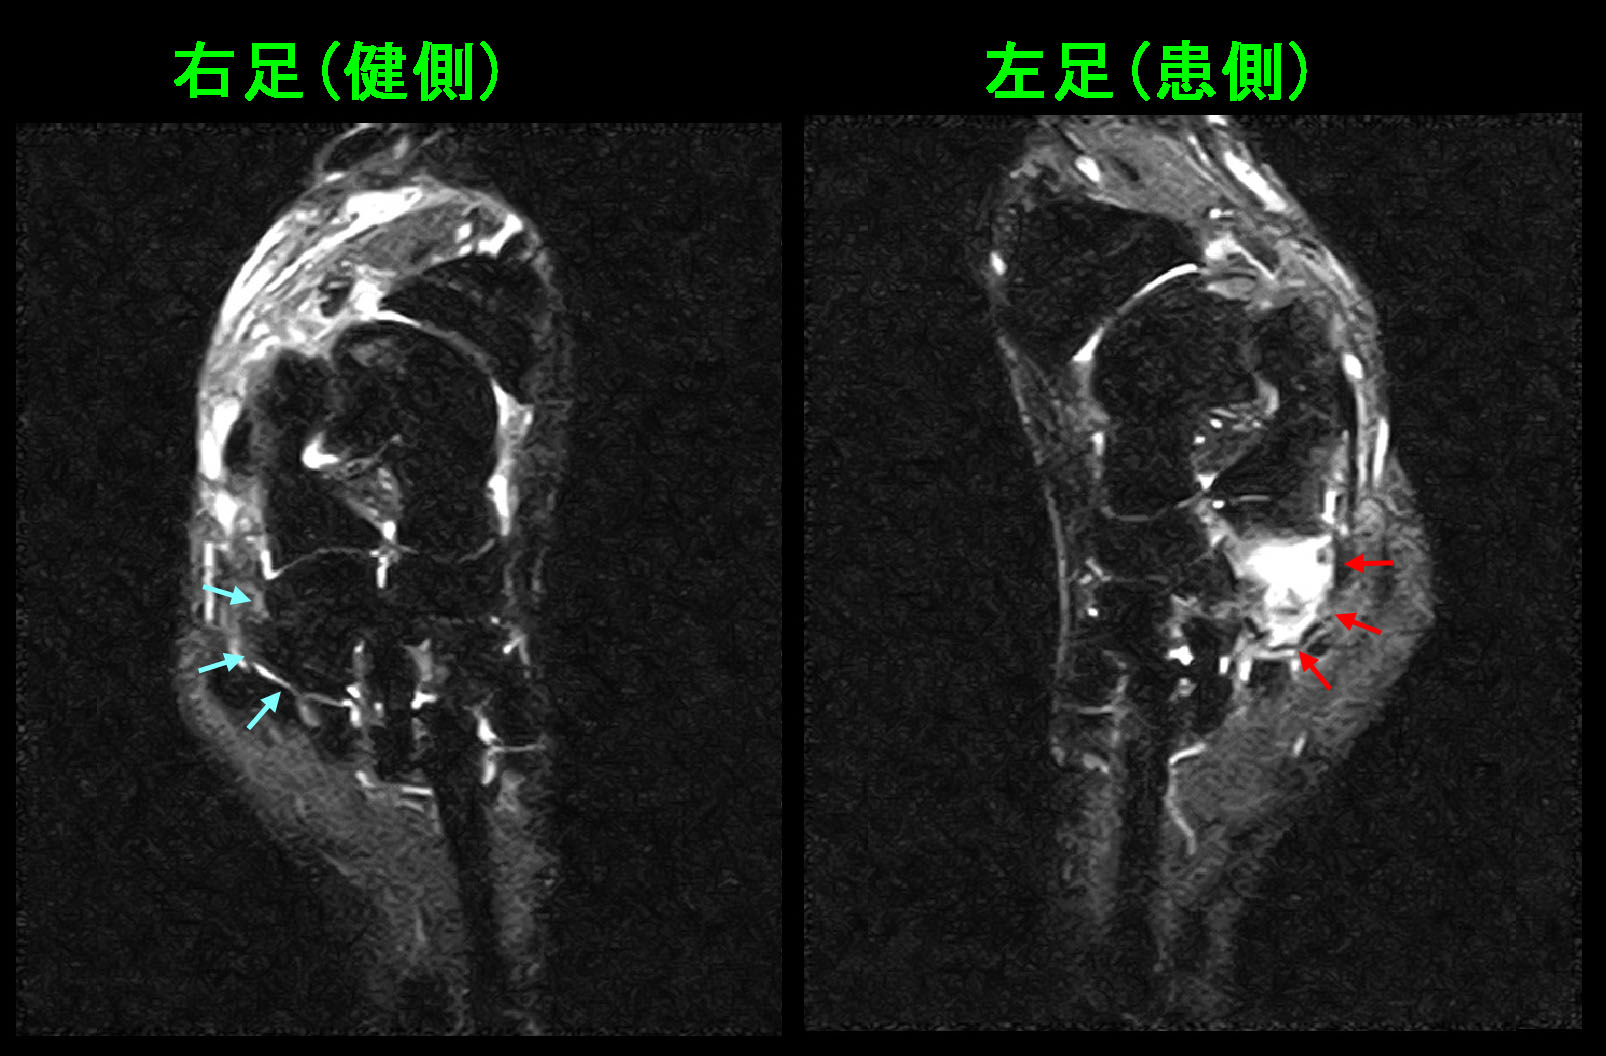

もう1例提示します。11才の小学5年生です。平成29年9月3日特設陸上部の選手に選ばれて、陸上競技の練習が始まりました。9月7日の練習で両側の足関節痛が発症し、1.2㎞の徒歩通学も困難となり、9月12日に当院を受診されました。

レントゲン像の赤丸部分が疼痛部位となります。レントゲン像では異常はありません。

11才陸上MR.jpg

MRI画像では赤矢印では明瞭な高輝度所見(顕在的疲労骨折所見と評価して良いと思います)が確認され、黄色矢印では軽度の高輝度所見(潜在的疲労骨折所見)が確認されます。このように急な運動負荷で骨は大なり小なり損傷するのです。この患者さんの場合、痛みは強くないと判断し、運動を休止せずに服薬のみで対応しましたが、陸上の大会まで練習は可能であったと報告を受けています。